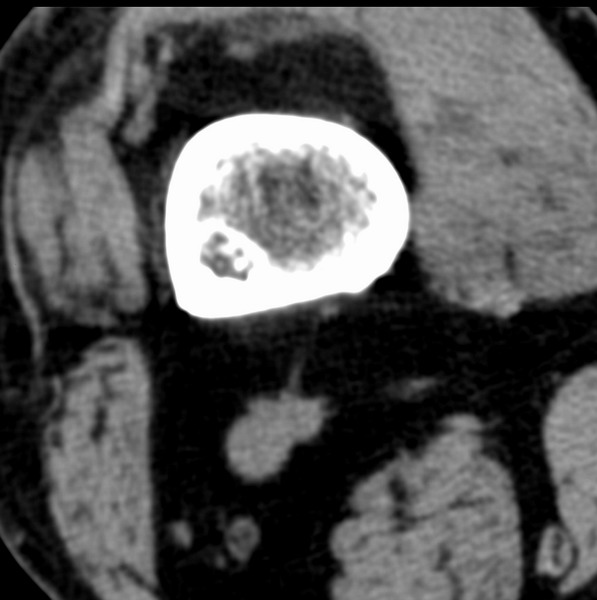

标题: CT21959:骨肿瘤请会诊。

右侧膝关节疼痛一月

男、48

股骨下段、胫骨上段。

1、股骨干骺端病变考虑干骺端纤维性皮质缺损愈后(非骨化性纤维瘤)改变,胫骨近端内生骨瘤(或干骺端纤维性皮质缺损愈后改变);

2、骨关节炎,骨质增生,股骨外侧髁退变性囊肿(关节面软骨下囊肿);

股骨干骺端病变考虑干骺端纤维性皮质缺损愈后(非骨化性纤维瘤)改变,胫骨近端内生骨瘤(或干骺端纤维性皮质缺损愈后改变);

多发内生软骨瘤!

股骨干骺端病变考虑非骨化性纤维瘤。

1、股骨干骺端病变考虑干骺端纤维性皮质缺损愈后(非骨化性纤维瘤)改变,胫骨近端内生骨瘤;